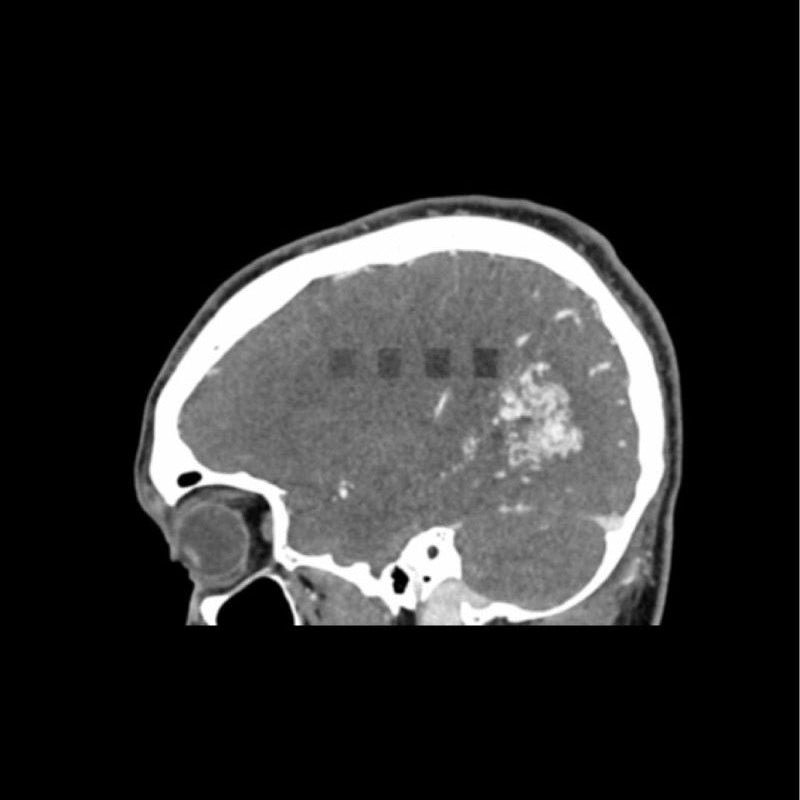

This phantom simulates a contrast medium enhanced head in arterial phase (CT angiography). It covers the vertex to the foramen magnum. The phantom has 10 low-contrast lesions in the centrum semiovale and the right hemisphere has an arteriovenous malformation.

- Arteriovenous malformation of the right hemisphere.

- 5 rod-shaped lesions on each side in the centrum semiovale at the periventricular and supraventricular level.

Lesion diameter: 10 mm

Lesion height: 10.5 mm

Lesion contrast: Approx. -60 to -20 and 20 to 60 HU at 120 kVp